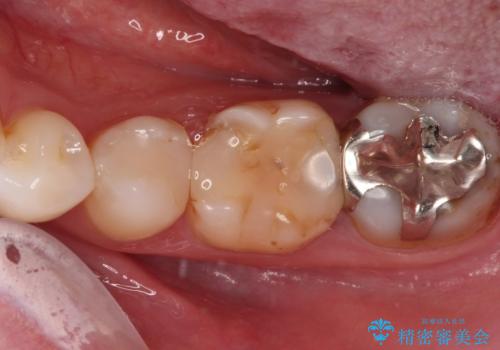

- 奥歯の詰め物や周辺の歯が欠けてしまったとのことで来院された患者様です。

上顎は、元々の詰め物が小さく、欠けた範囲も大きくなかったため、セラミックインレーにて修復治療を行うこととしました。

一方下顎は、元々のむし歯の範囲が広かったため、長期的な予後を踏まえ、セラミッククラウンにて補綴治療を行うこととしました。